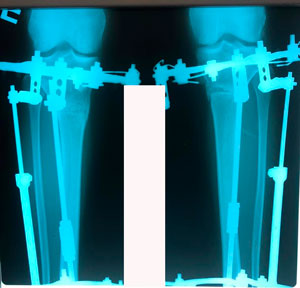

на фиксации

IMG_6691-25-10-19-11-13.JPG

IMG_6688-25-10-19-11-13.JPG